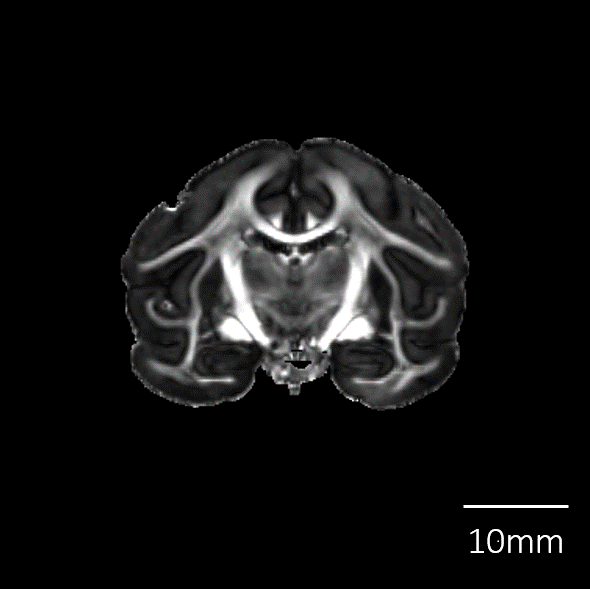

脳標本画像 Brain MRI Images

| T2強調画像 |

![]() |